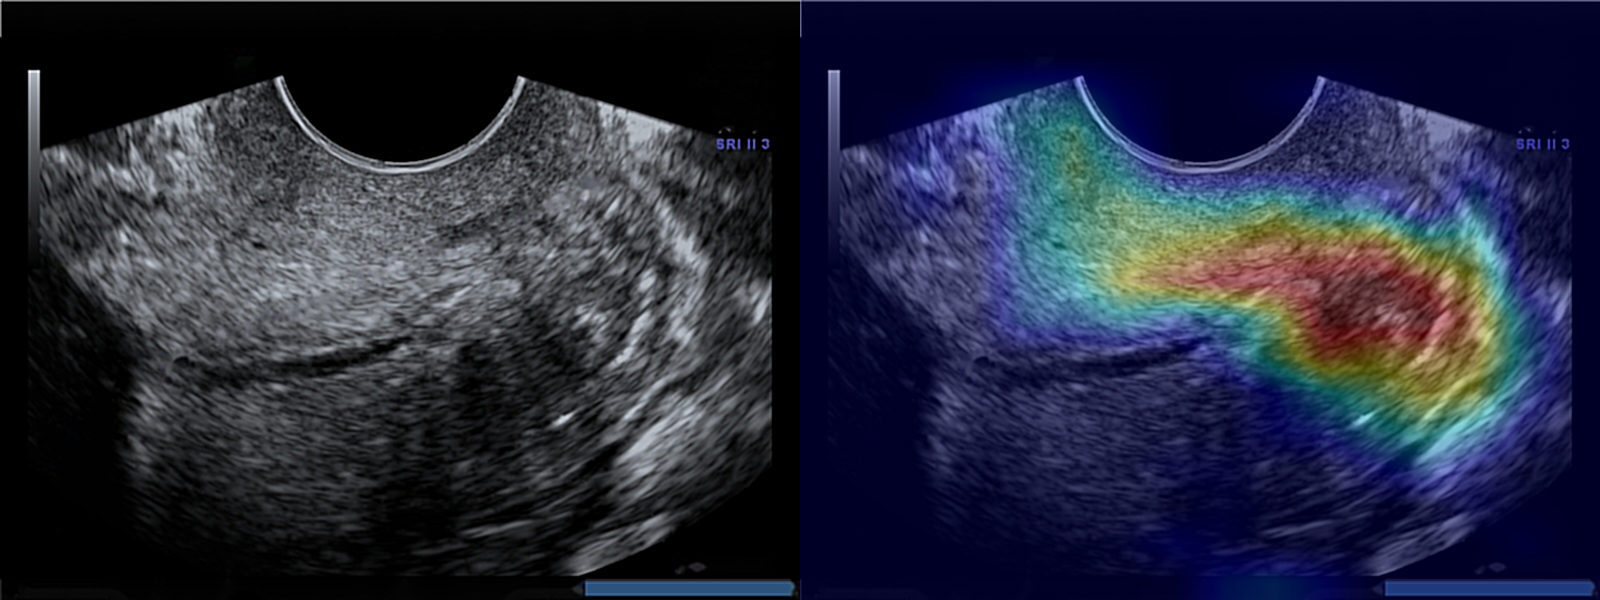

Visualization: In order to increase the understanding of the predictions of spontaneous preterm births performed by the convolutional neural network on ultrasound images, we have visualized them by using the gradient weighted class activation mapping (Grad-CAM) method. This method is used for visual interpretation of deep neural networks through a gradient-based location, highlighting the most interesting regions in the image for prediction. Grad-CAM uses gradient information provided to the last layer of the CNN to allow the viewer a greater understanding of the importance of each neuron’s region of interest. By using Grad-CAM, it is possible to visualize which features in the cross section contribute to judging the class. For this purpose, we used the original implementation of the work of Selvaraju et al. [13].

3.3 Grad-CAM

It was found by Baños et al. [14] that information extracted from the region along the length of the anterior cervical stroma is relevant to control vs preterm classification. In addition, Pachtman et al. [15] proved that the region along the length of the anterior cervical stroma and the analysis of its relative organization of cervical collagen fibers may have the capacity to identify preterm birth. To the contrary, Grad-CAM shows the preterm class is classified based on the lower segment of the cervix, close to the ectocervix. We can note that during classification, the neural network focuses on the heterogeneity of the density of tissues around the cervix. For the control class, our model is focusing on the top part of the largest homogeneous region in middle part of anterior cervical lip, which is the part of the cervix closest to the transducer. Examples of Grad-CAM results can be seen in Figure 5 for the preterm and control class.